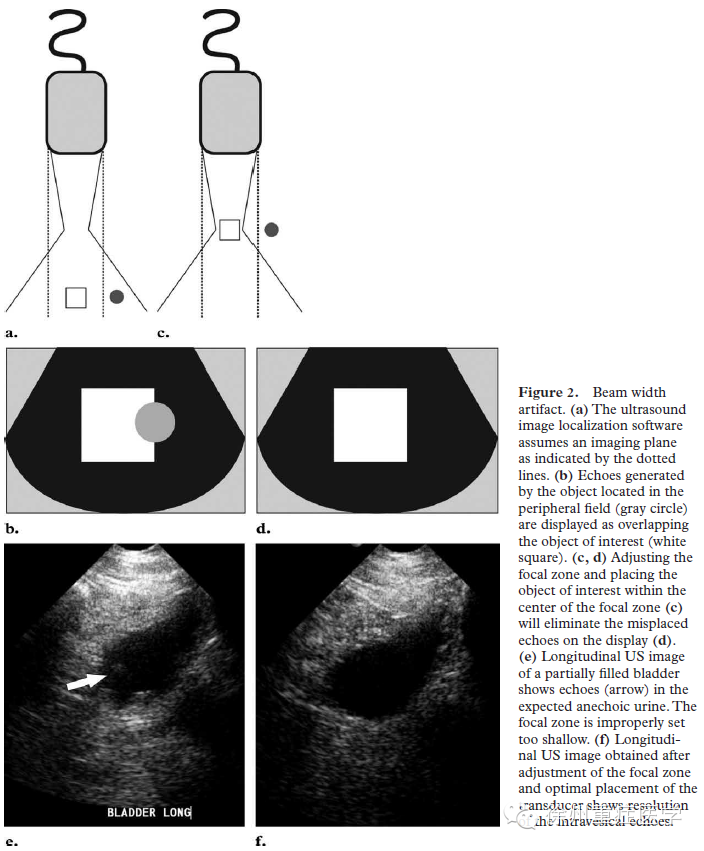

振子发射超声大部分以0°角发射(主瓣),少数出现偏斜放心发射,即旁瓣(side lobe)。(图1)超声在形成图像时默认为回声均来自于0°方向的回声。声束宽度伪像可以通过调整声束形状进行识别。声束的近场宽度和探头尺寸相似,最窄处出现在焦点,偏斜扩大的部位出现在远场。远场声束的宽度可以超过探头的尺寸。当位于旁瓣区的强回声,因与焦点位置的不同而产生不同的图像(如图2)。旁瓣为低能量、放射状包绕主瓣周边的声束。它的能量多来源于径向排列的压电晶体,因此多见于线性阵列探头。当位于旁瓣的强反射源时,回声会被错误是认为来自于主瓣。如图3。作为一种声束宽相关的伪像,腹部探测时,腹壁的筋膜和肌层都是平整的界面,常出现混响伪像,出现在声像图的浅表部位,尤其在胆囊和膀胱等液性器官的前壁,更为明显(图3-2